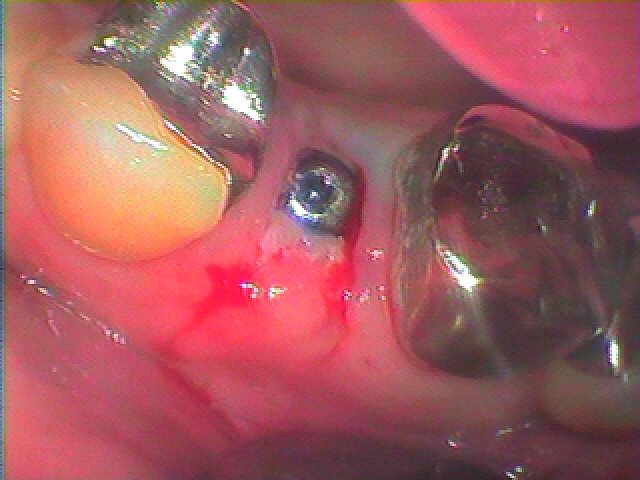

1週後には抜糸を行いました

1週後になります